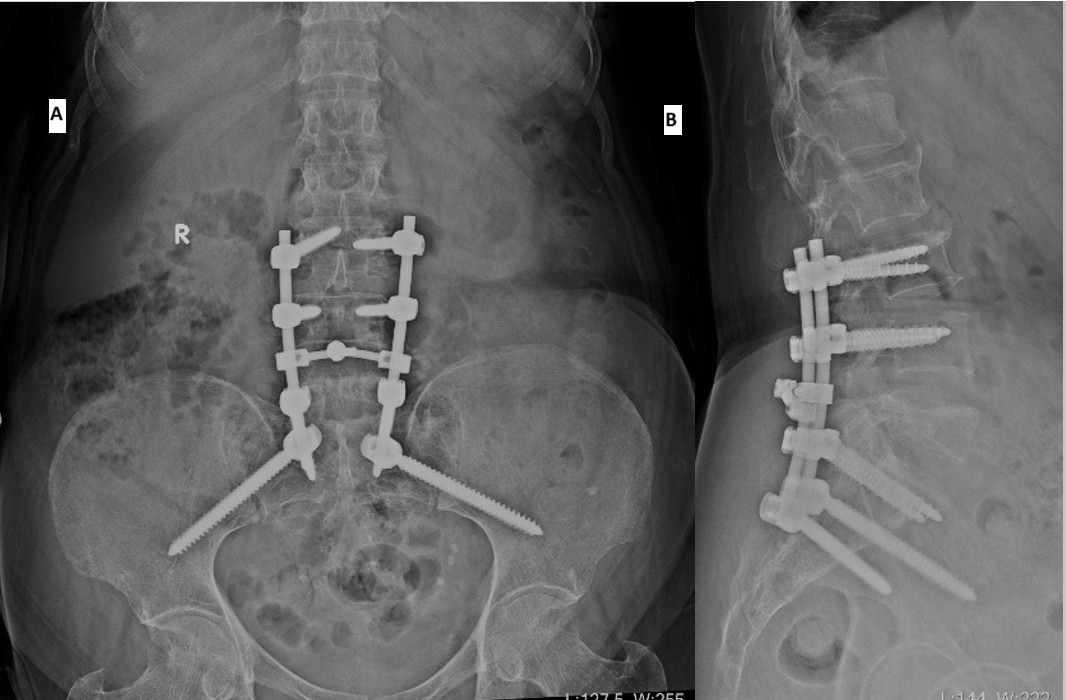

A multidisciplinary tumor board, including specialists from orthopedics, pathology, oncology, and radiology, reviewed the case and recommended surgical decompression of the spinal cord. The patient underwent posterior decompression at L5, pedicle screw fixation at L3, L4, S1, and iliac screw fixation at S2 level. She tolerated the procedure well, and her post-operative course was uneventful. Intravenous zoledronic acid was administered in the post-operative period. Wound inspection during follow-up revealed a clean and healthy surgical site (Fig. 5).

Figure 5: Post-operative radiographs (a) anteroposterior, (b) lateral views.